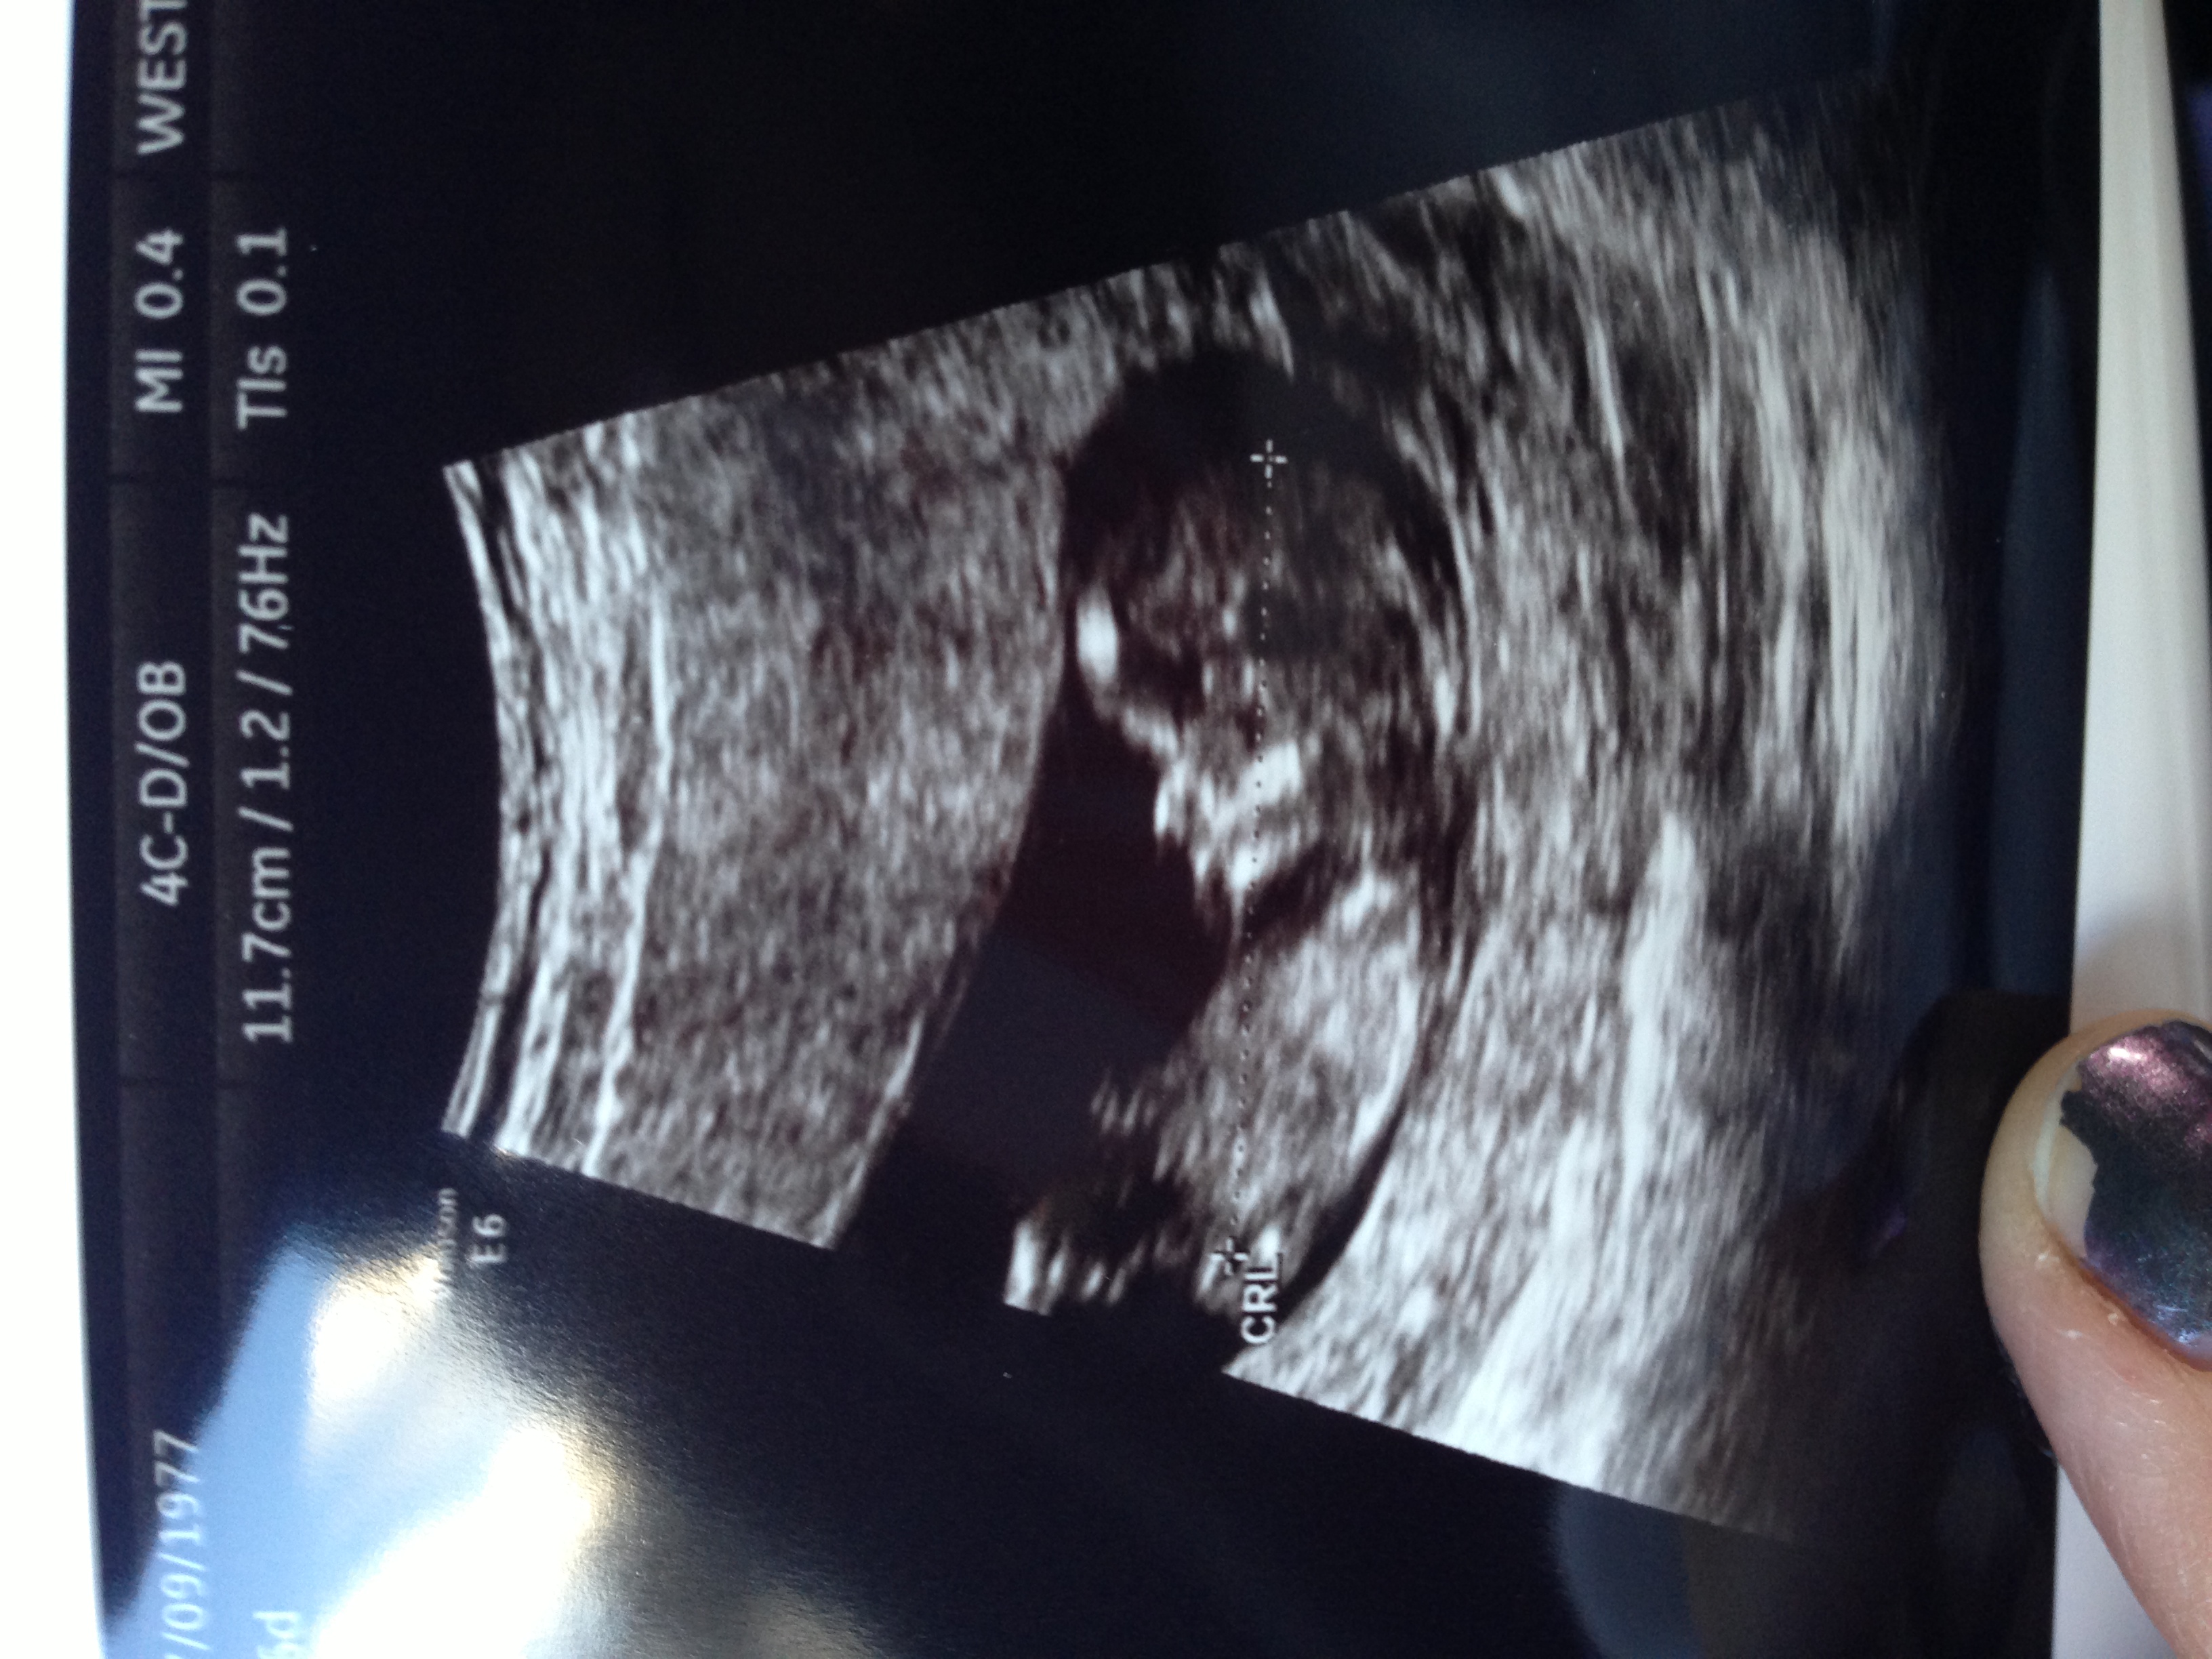

12 weeks-any more boy or girl guesses? Much appreciated!

I'm not seeing a nub.